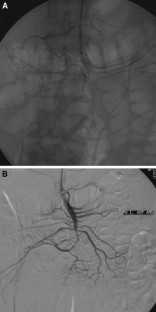

Superior Mesenteric Artery Embolism Treated with Percutaneous Mechanical Thrombectomy

A case of acute superior mesenteric artery embolism treated with percutaneous thrombus aspiration is described. A 63-year-old man with chronic atrial fibrillation was admitted to the hospital with progressive abdominal pain. Computed tomography angiography revealed an occlusion of the distal part of the superior mesenteric artery. The patient was effectively treated using transaxillary percutaneous mechanical thrombectomy using a 6F Aspirex thrombectomy catheter.

Fig. 1

Fig. 2